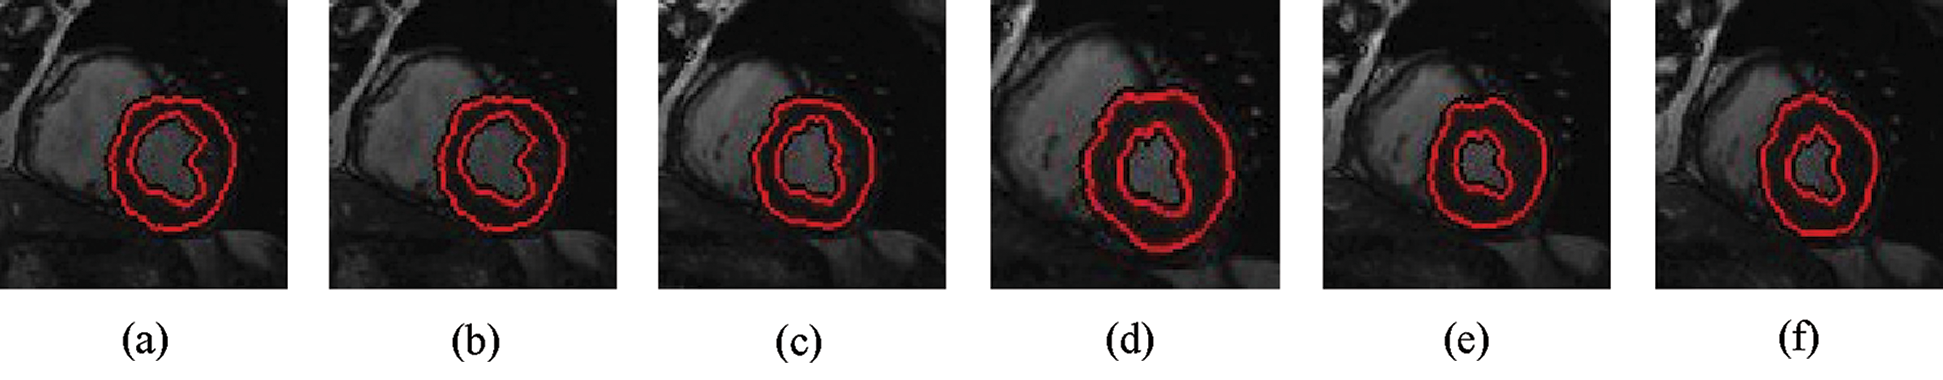

The experimental results are categorized into two distinct sections to underline both the segmentation and psoriasis lesion localization results. The presented results of this paper were obtained through using different 6 techniques to 300 sets of CVD. In this paper, multi-axis CMR database was used in three axes for 6 case studies to provide the results of various segmentation schemes. In this section, the employed techniques for studying and segmenting medical images are executed using MATLAB. Figs. 1a–1f present the Caselles segmentation technique results. These results indicate that this technique gives better results when the initialization step is suitable and the image has a high intensity gradient at the edge between the cavity and the myocardium of LV. It is also clear from the results that the blood pool segmentation depends on the boundary features. Both of Li and Bernard segmentation techniques show a wide band segmented results that are not reasonable to the blood pool segmentation as shown in Figs. 2 and 3. This is apparently visible in the Bernard segmentation technique where the segmentation partitions of each slice to bright regions and dark regions cannot separate the LV cavity from other parts of the image. The relationship between each pixel and its adjacent neighbors is considered. As it could be seen from Figs. 4a–4f, the blood pool of LV is purely delineated. That is the resulted segmented image of the Chan-Vese technique appears well-defined. Based on the obtained results, one can say Chan-Vese technique works well with homogenous regions such as cardiac images. In addition, the resulted segmented slices appear of high smoothing degree as well. The segmented images from the blood pool of LV obtained using the Lankton-Yezzi segmentation is presented in Figs. 5a–5f. As it could be seen from these figures, the quality of the segmentation process using the Lankton-Yezzi technique depends on the initialization. As it could be seen from Figs. 6a–6f, the two cycles of Shi-Karl segmentation technique produce good quality segmentation to the LV blood pool.

Figure 2: Sample results of Li technique

Figure 3: Sample results of Bernard-Friboulet technique